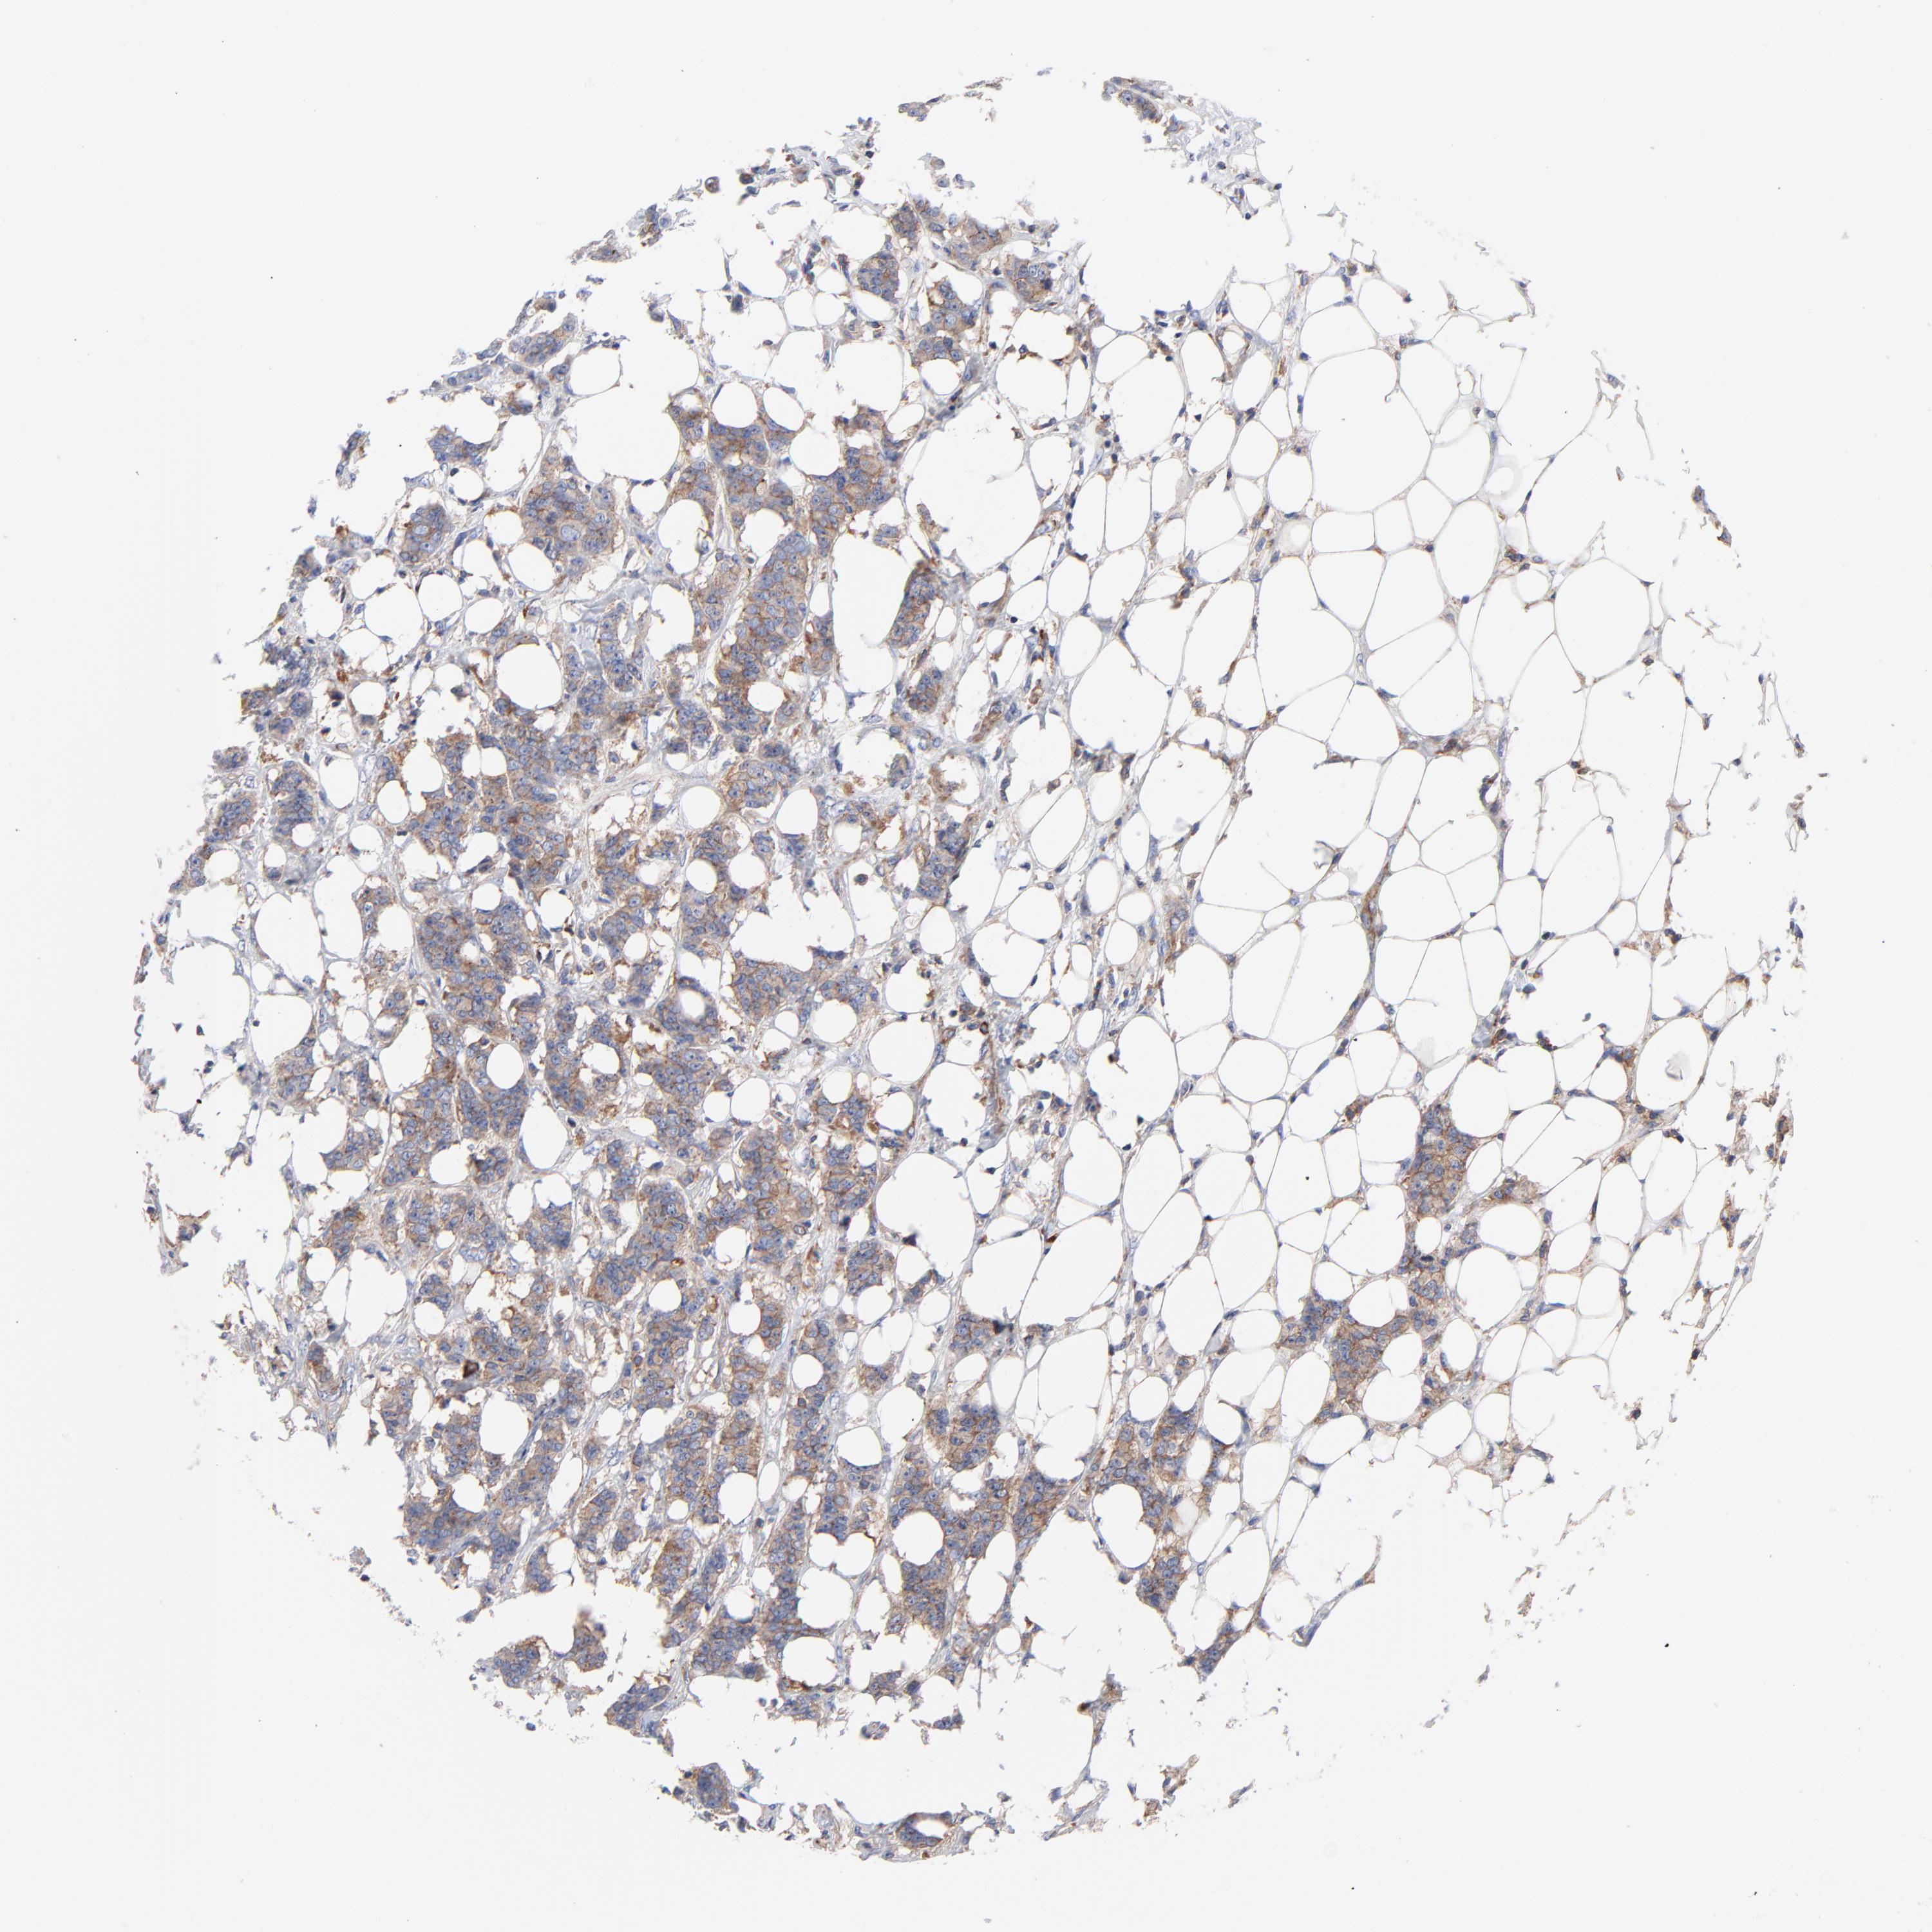

CANCER BREAST CANCER Show tissue menu

BRCA TCGA BRCA VALIDATION PROTEIN EXPRESSION